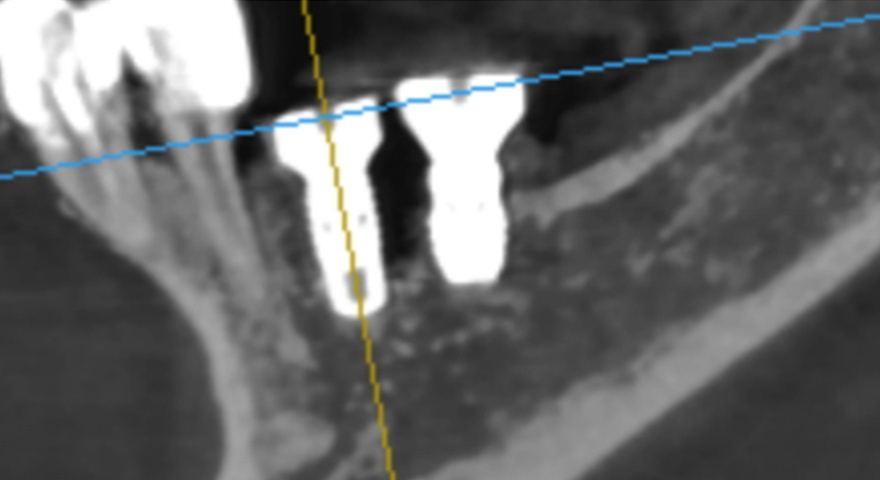

У рамках проспективного дослідження троє пацієнтів із частковою або повною адентією отримали загалом 17 імплантатів, з яких три — в ділянки з вираженими дефектами букальної кістки. Ці імплантати були вилучені через шість місяців для аналізу. При аугментації застосовували формопластичний остеоматеріал (S1) та гранульований матеріал (BOSS), які покривали колагеновою мембраною (COLLA). Всі матеріали були бичачого походження. Стан кісткової інтеграції аналізували гістологічно та гістоморфометрично.

Після проведення стандартної імплантації в ділянках з оголеною різьбою було застосовано техніку DUK: на імплантат наносили спочатку пастоподібний матеріал, далі — гранули, після чого укладали мембрану та закривали клапті швами без натягу. Всі пацієнти отримували антибіотики (амоксицилін) та знеболення (ібупрофен), а через шість місяців — проходили контроль та біопсію ділянки.

Гістологічні зрізи трьох отриманих імплантатів — демонструють регенерацію букальної кістки через шість місяців після імплантації. Чорна горизонтальна лінія позначає найбільш корональну точку контакту букальної кістки з імплантатом, а червона лінія вказує на початковий рівень букальної дегісценції під час встановлення імплантата, що дозволяє оцінити утворення нової кістки.